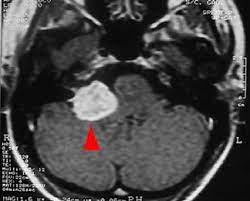

Tumores del Ángulo Ponto Cerebeloso

Tumores del ángulo pontocerebeloso son tumores ubicados en un área compleja en la base del cráneo, dentro de la fosa posterior, rodeados de nervios, vasos sanguíneos y tejido neural vital. Estos tumores en general son benignos, sin embargo, dada su ubicación, representan entidades de difícil tratamiento para lograr su extirpación o des vitalización sin producir secuelas importantes. El Ángulo Ponto-Cerebeloso es una zona de la base del cráneo posterior (zona de la nuca), en íntima relación con el cerebelo y la protuberancia o puente (ponto) del tronco cerebral, de donde se deriva este nombre de ponto-cerebeloso. Existe un ángulo ponto-cerebeloso por cada lado de la cabeza, limitados por el cerebelo en la zona medial, el hueso de la base del cráneo hacia el lado, y estructuras nerviosas y vasculares muy delicadas e importantes hacia arriba, abajo, adelante y atrás.

- Los más frecuentes son los tumores llamados schwannomas (llamados a veces neurinomas) de la rama vestibular del octavo nervio craneano, tumores nacidos de células que forman este nervio (células de Schwann) que se reproducen de manera anormal y exagerada, produciendo el tumor.

- Otro tipo de tumor de la zona son los meningiomas, tumores nacidos de las meninges que recubren las estructuras nerviosas de esta región. Se dice que son tumores benignos porque no tienden a infiltrar las estructuras vecinas ni tampoco producen siembras o metástasis, pero tienden a crecer localmente hasta tamaños muy grandes cuando se detectan tardíamente y desplazan y comprimen órganos vitales, pudiendo comprometer la funcionalidad normal e incluso la vida en muchos casos.